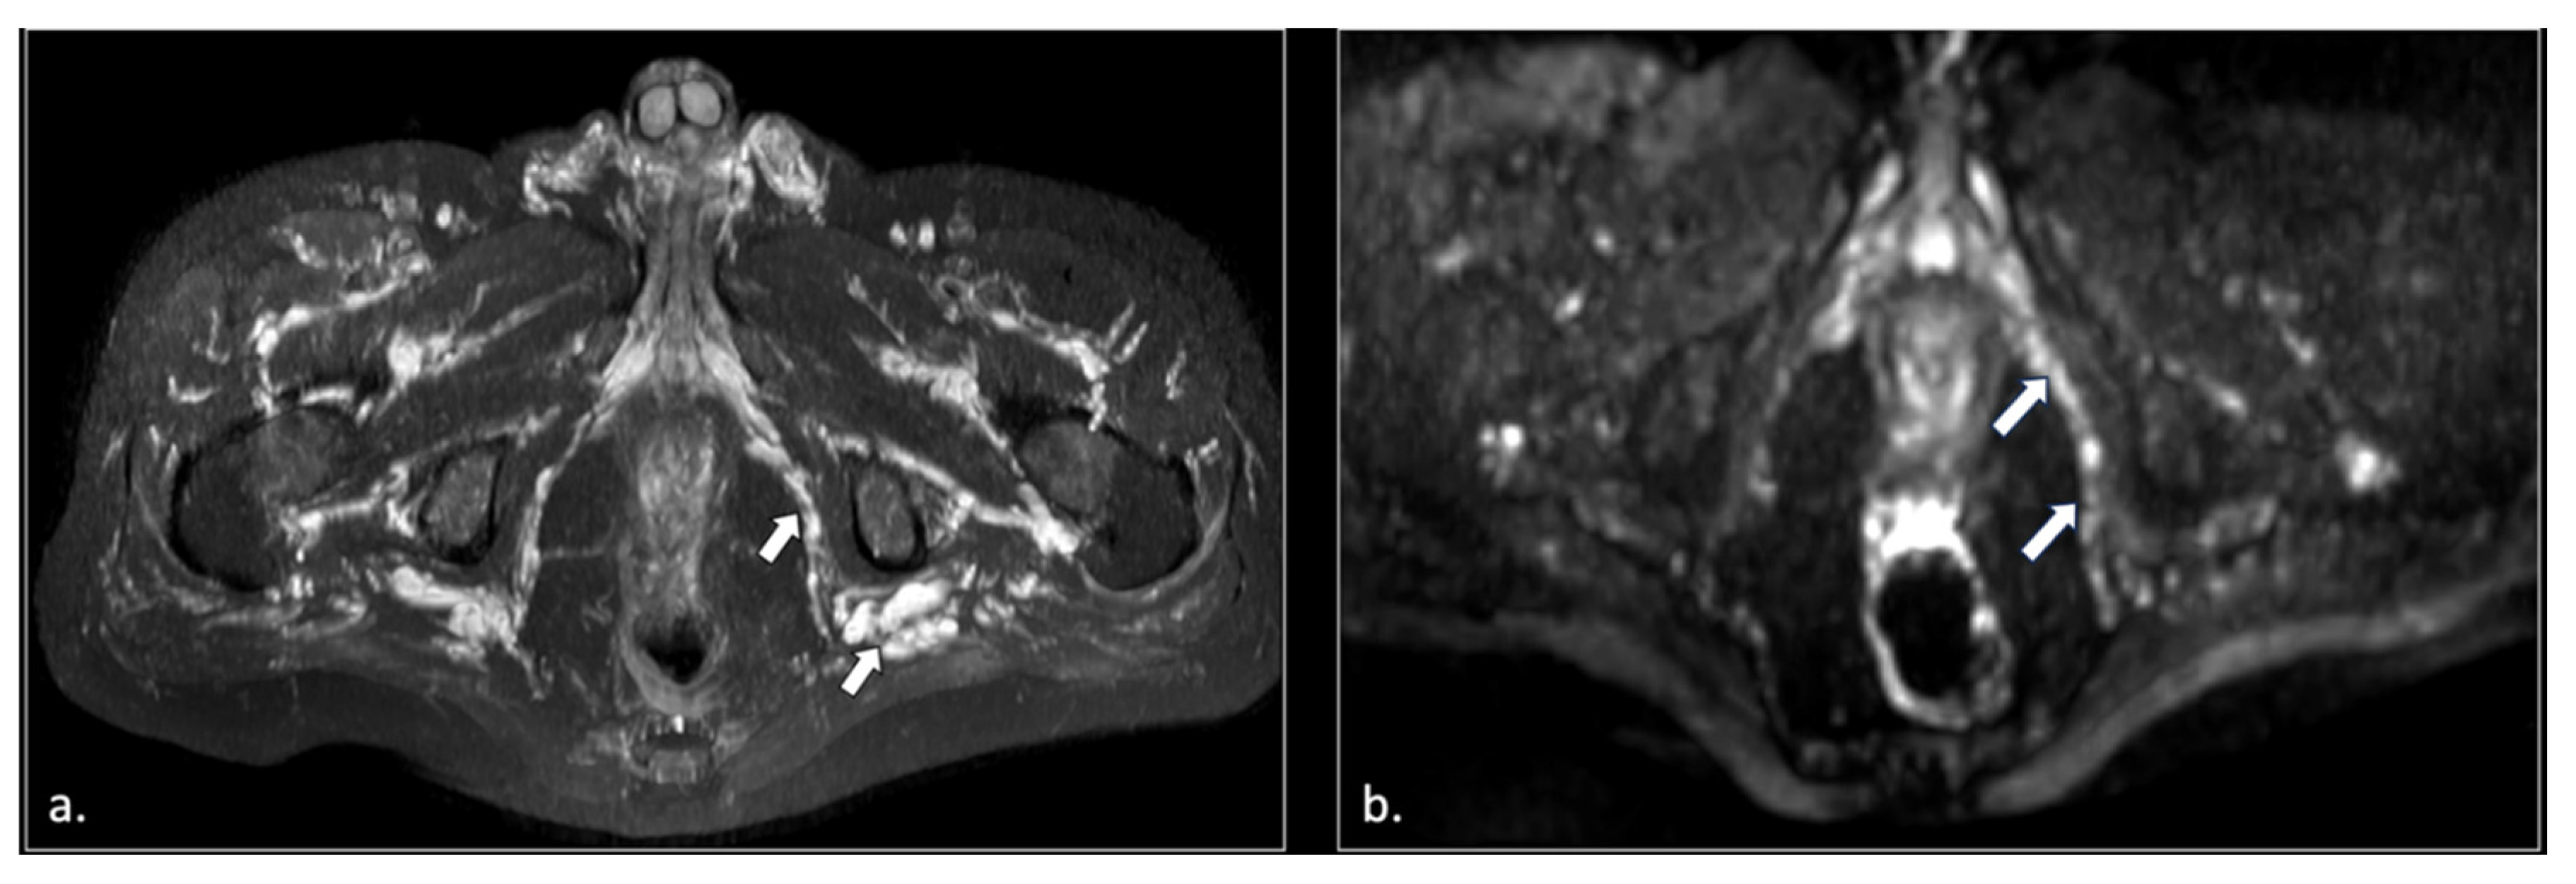

Figure 4.

32-year-old man with relapsing pudendalgia after decompressive surgery on both pudendal nerves. (a) Axial T1-weighted image, obtained at the level of ischial spine, shows fibrosis along the extra-pelvic course of both pudendal nerves (arrows). (b) Axial T1-weighted enhanced subtracted scan demonstrates enhancement along the course of the nerves (arrows).

Figure 5.

71-year-old male with chronic pudendalgia. (a) STIR Maximum intensity Projection (MIP) scan shows diffuse venous dilatation of the lower pelvis, including varices of pudendal veins (arrow). (b) b600 DWI Maximum Intensity Projection (MIP) shows enlargement and hyperintensity of the left pudendal nerve (arrow).